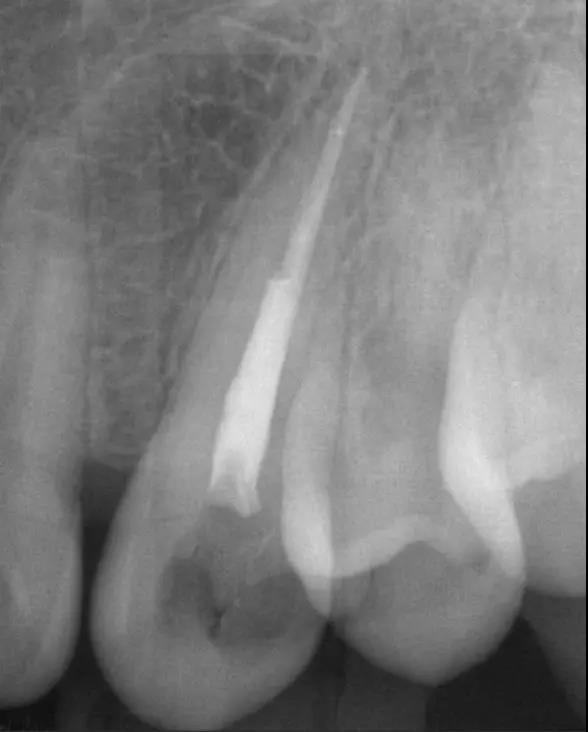

①小牙片:顾名思义,这种牙片很小,只能显示牙齿局部,但它能将局部放大,更加清晰地看到牙齿情况。根管治疗中,医生常需要小牙片辅助判断牙齿疼痛的原因。